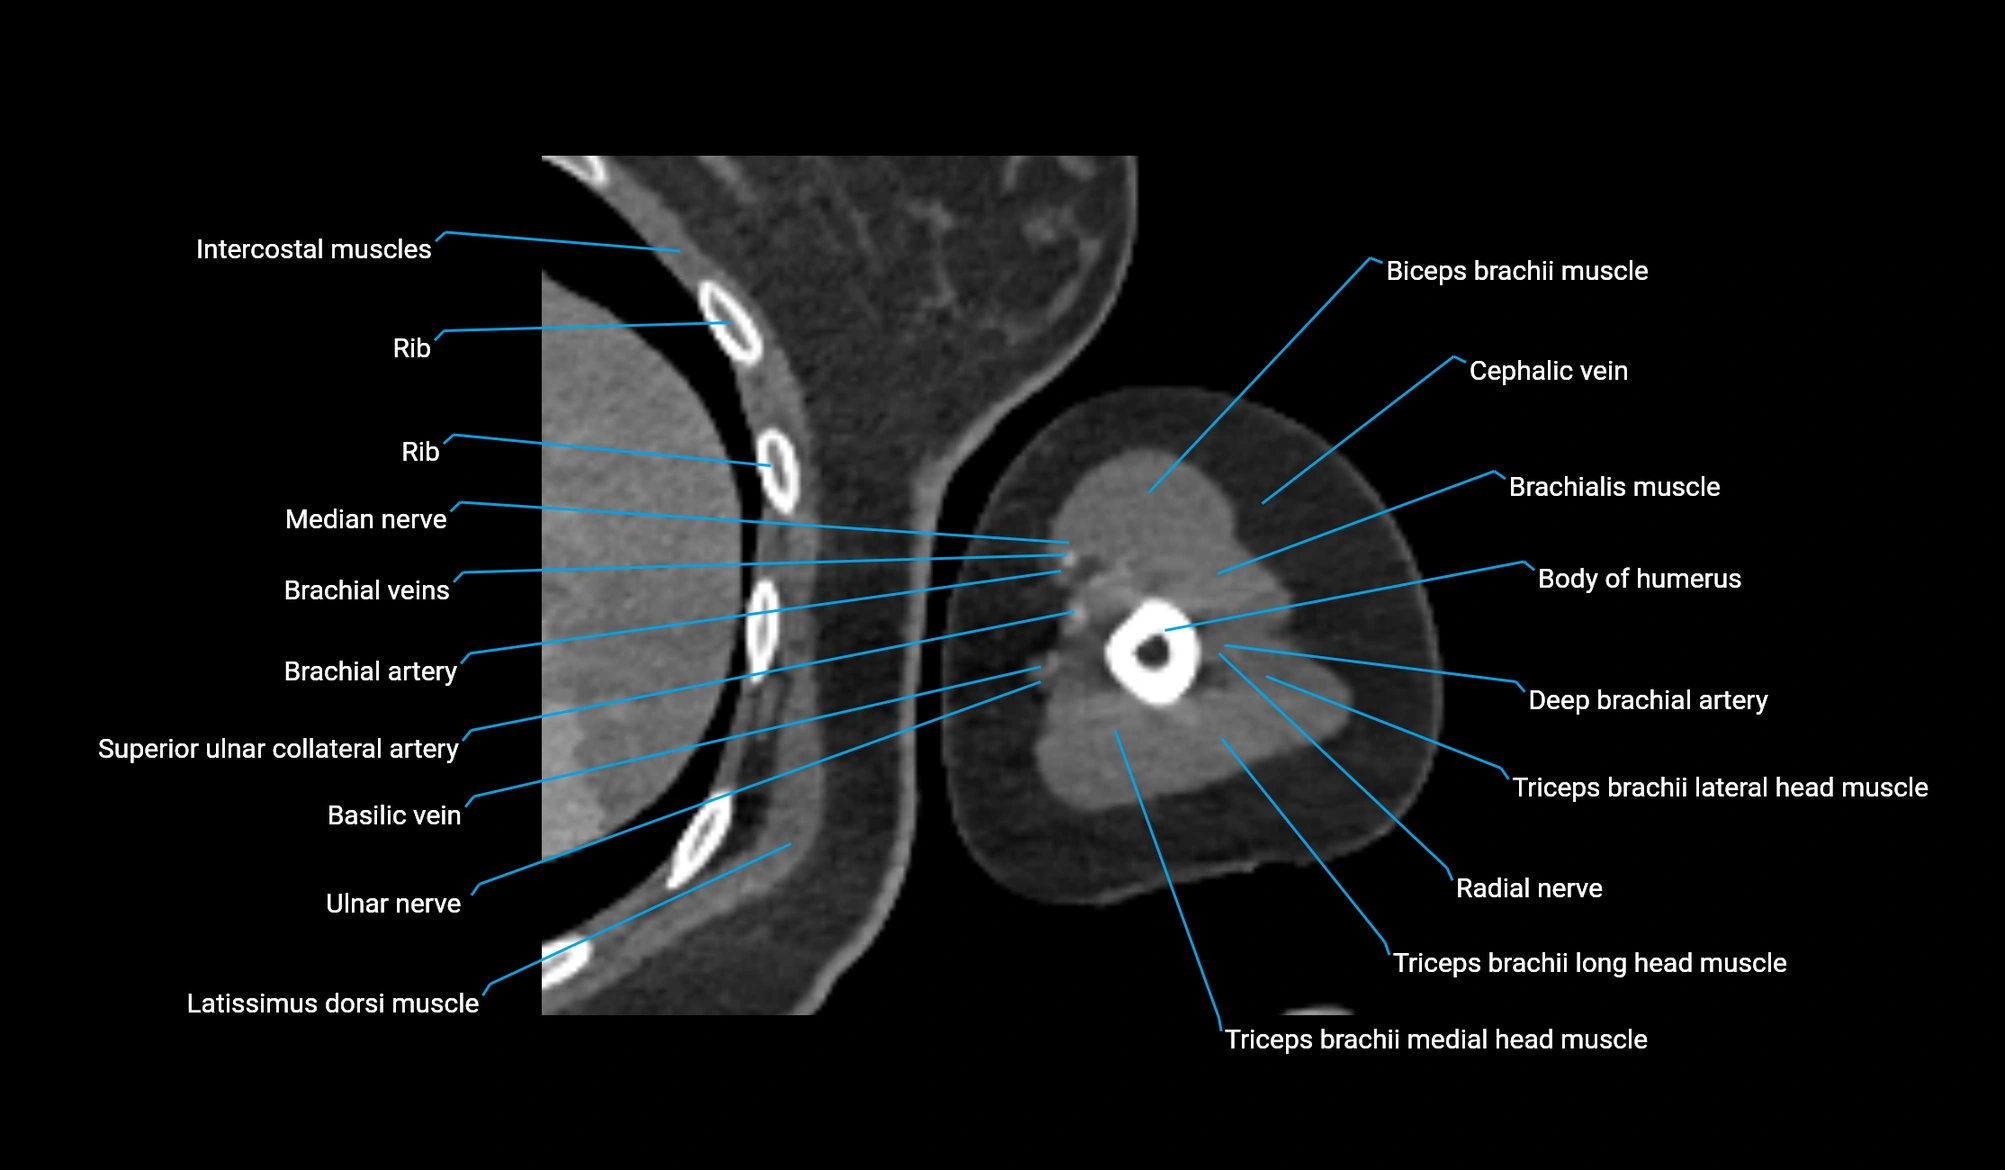

CT image